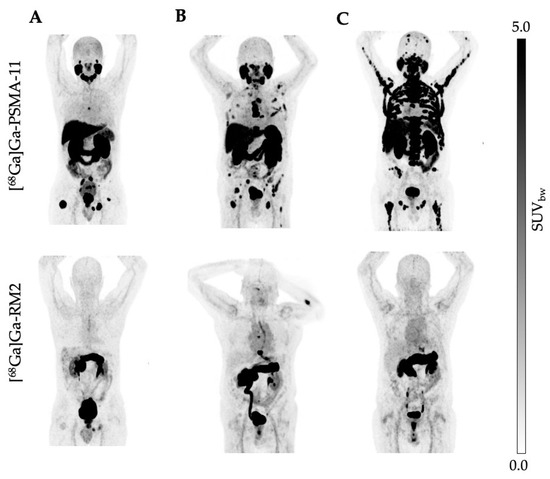

3.2. Uptake Comparison between [68Ga]Ga-PSMA-11 and [68Ga]Ga-RM2